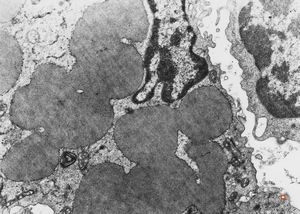

M,58y. | spleen - thesaurismosis of unknown origin … postmedicamentous?